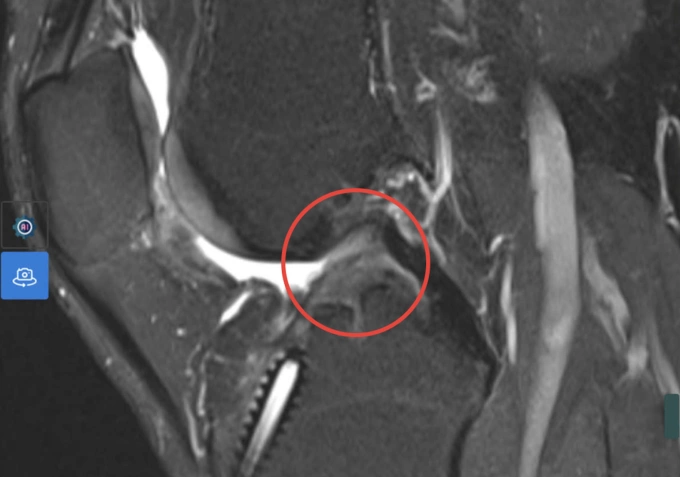

Kết quả chụp MRI cho thấy dây chằng chéo trước đã đứt hoàn toàn. Ảnh: Bệnh viện Đa khoa Tâm Anh